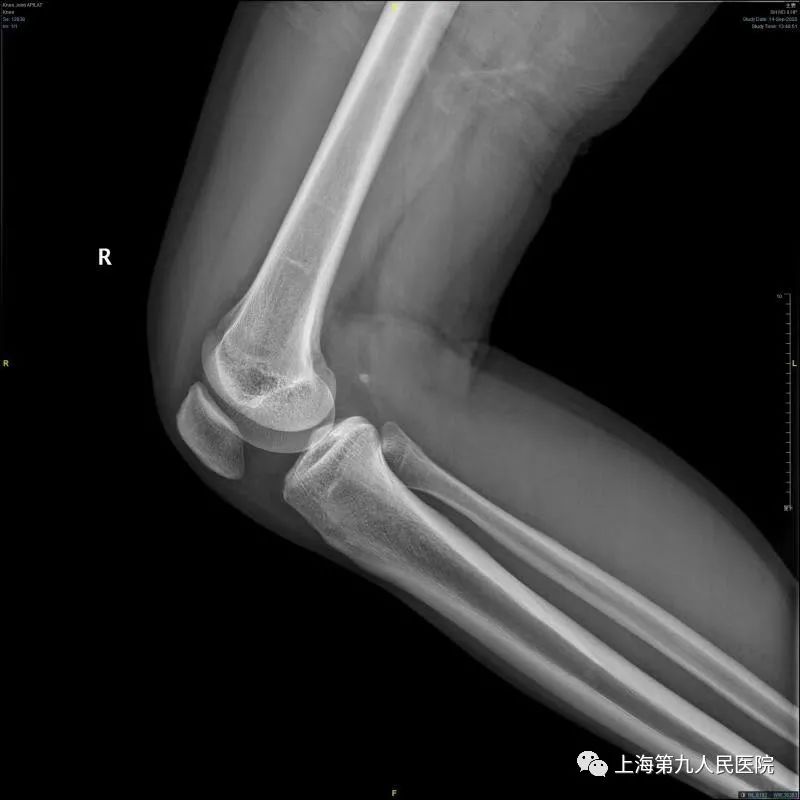

好多膝关节疼痛的朋友到医院寻诊时,医生多会让做一个膝关节的X线检查,就是下方这两张X线片,一张正位片、一张侧位片。

每个人的膝关节是由3块骨头加上一些软骨、韧带等软组织组成的。这3块骨头分别是股骨(大腿骨)、胫骨(小腿骨)和髌骨(膝盖骨)。每块骨头的表面有一层软骨,软骨富有弹性而又光滑,并且没有神经支配,有利于骨头之间无痛而又圆滑的摩擦活动;另外,在股骨和胫骨中间有两个垫片,叫作半月板,有调节冲击力的作用,并让骨表面之间更贴合。在日常生活中,健康的软骨和半月板保证我们的膝关节能够顺畅的完成各种活动。二

全身任何关节都可能发生骨关节炎,由于膝关节使用频繁、活动多、承受体重大等因素,发生骨关节炎更为常见。发生膝骨关节炎的朋友通常表现为关节疼痛、僵硬、肿胀,活动后疼痛加重,休息后有缓解,遇见寒冷、潮湿环境疼痛会加重。有些人平时走路还可以,但是上下台阶、起坐马桶或椅櫈困难;有些人平时疼痛症状轻微,而在一个轻微的扭伤后就出现关节显著的疼痛肿胀,长时间不能缓解。比如,66岁的王阿姨,平时身体没啥毛病,就是左侧膝盖痛了5年多,时好时坏,一开始出现关节疼痛后休息几天就好了,平时也没当回事。后来上下楼梯疼痛明显,平地上也走不远了,还变成了罗圈腿,最近半年关节疼痛更明显,有时晚上睡觉也疼,这样就很少出家门,生活影响很大。1月前到医院检查,拍X线片看到膝关节已经明显退变,缝隙变窄,磨损严重,骨质增生。